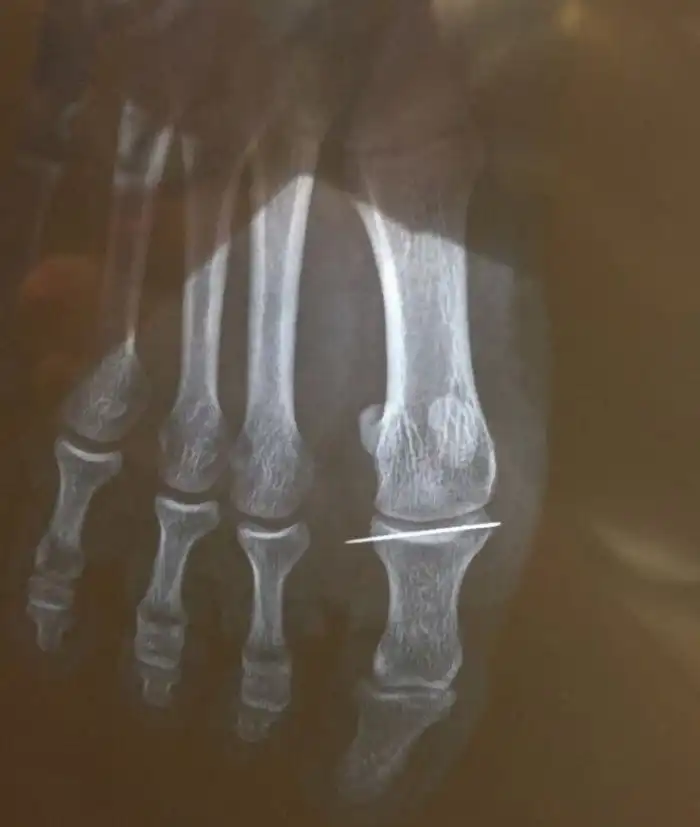

На игле

Вот к чему приводит рукоделие без наличия нужных навыков.